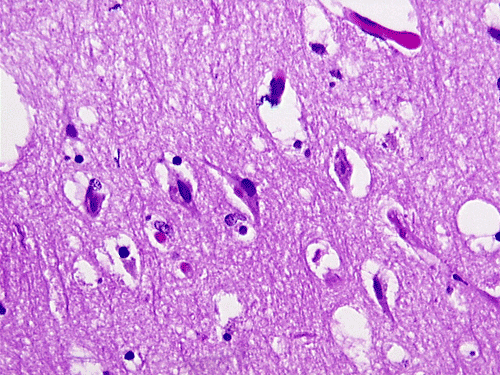

The overall tissue preservation is less than optimal because of postmortem autolysis. Panel A and B are taken from the cerebellum. The molecular layer, Purkinje cell layer, and internal granular layer are included (Panel A). Solitary eosinophilic intracytoplasmic inclusions of variable size are present in the Purkinje cells. No inflammatory cell infiltration is present in the cerebellum. The vacuolar spaces (Panel B) is partly due to autolysis and partly due to hypoxic/ischemic changes. Pyramidal cells in the hippocampus (Panel C), cortical neurons in parietal lobe (Panel D) and other neocortical areas adopted an elongated and contracted contour with loss of nuclear details. These are histologic features consistent with hypoxic/ischemic changes. Similar to the cerebellum, solitary eosinophilic cytoplasmic inclusion bodies are present and there is no inflammatory cell infiltration. Multiple eosinophilic cytoplasmic inclusion bodies within a single neuron are occasionally found. Some of these neurons containing multiple inclusions from the substantia nigra are illustrated in Panel E. Although inflammatory cell infiltration is scant in the cerebrum and cerebellum, perivascular chronic inflammatory cell infiltrations are common in the medulla (Panel F and G), in the paravertebral sympathetic ganglion (Panel H and I) and in the spinal cord (not shown). Intracytoplasmic inclusions, however, are not found in the medulla, spinal cord, and paravertebral sympathetic ganglion. Under the electron microscope, rod-shape or bullet-shaped viral particles are found (Panel J).

The brain and spinal cord may appear swollen but are usually free of focal lesions. Histopathologically, rabies is a widespread polioencephalomyelitis. Leptomeningeal and parenchymal perivascular lymphocytic infiltrations are usually present but often not intense. Neuronophagia can also be seen. The amount of inflammation of the case under discussion is, in fact, on the intense side of the scale. The pathognomonic Negri bodies 10, 11, 12 are sharply delineated, round to oval, eosinophilic, neuronal cytoplasmic inclusions; first described by Negri in 1903 10. These inclusions are often solitary but may also be multiple in a single neuron. Lyssa bodies refer to less well delineated and more pleomorphic neuronal cytoplasmic viral inclusions. Babes’ nodules refer to clusters of microglia that remain after destruction of neurons. When immunohistochemistry is employed, the distributions of viral antigen are far more extensive than that estimated by conventional light microscopy 13. Negri body and rabies viral antigen as demonstrated by immunohistochemistry are most commonly seen in large neurons of the hippocampus (Pyramidal cells), cerebellum (Purkinje cells), thalamus, basal ganglia, cerebral cortex and in the brain stem, especially gray matter of the pons and medulla. They are also found in spinal cord motor neurons and dorsal root ganglion, especially in the paralytic form.  Immunohistochemistry also demonstrated rabies viral antigen in astrocytes and oligodendrocytes 13. Characteristically, a striking discrepancy between the degree of inflammation and amount of inclusion bodies is observed, as in our case, in many cases.